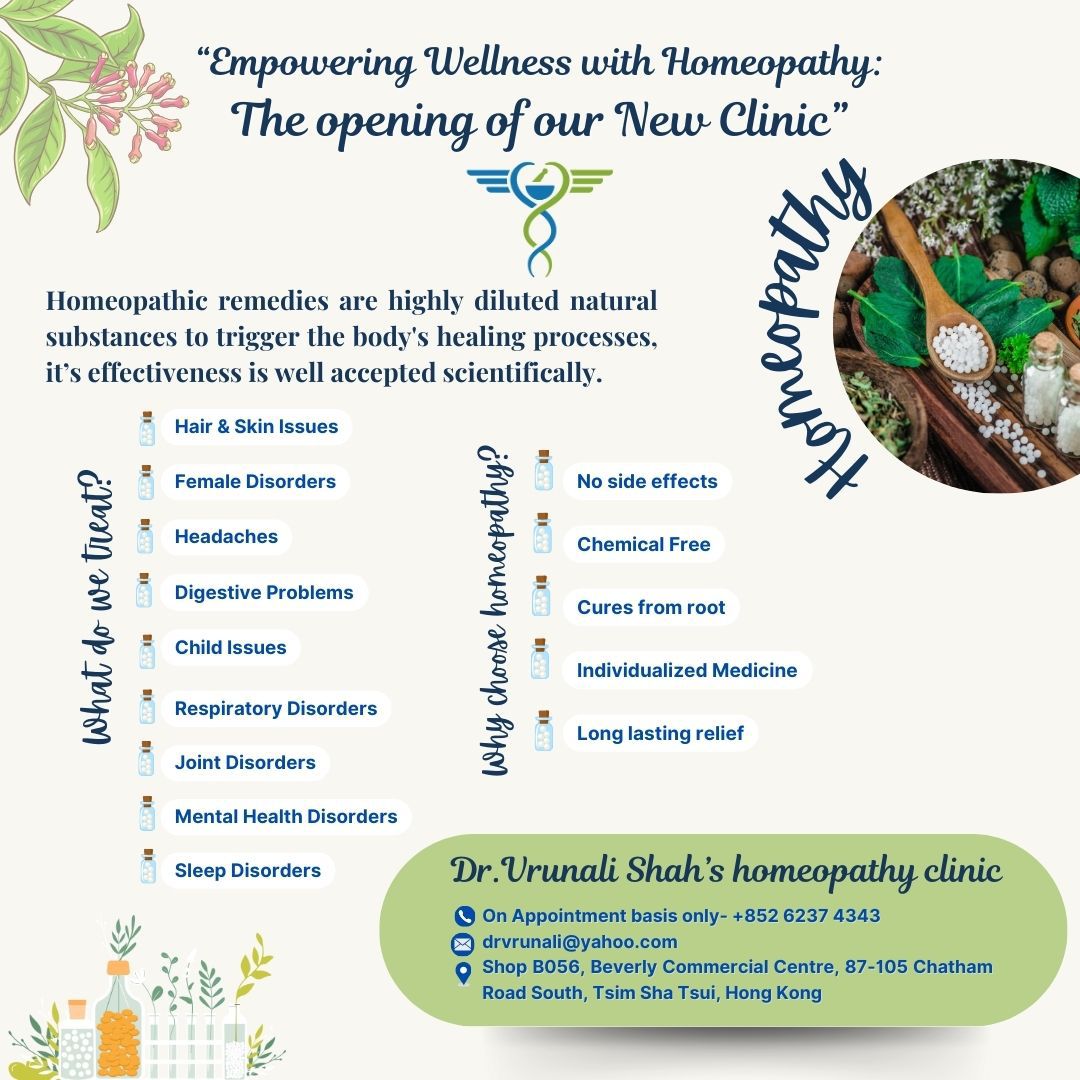

Dr. Vrunali has been practicing Classical and Clinical Homoeopathy for the past 25 years, encouraging individuals towards holistic health using natural remedies by combining her homoeopathic skills with Bach Flower Remedies to treat both physical and mental health.

Safe and Non-Toxic :

Suitable for all ages, including infants, pregnant women, and the elderly.

Non-Invasive :

Focuses on stimulating the body’s self-healing mechanisms.

Effective for Chronic and Acute Conditions:

Addresses a wide range of conditions such as allergies, migraines, stress, and skin disorders.

Complementary Medicine:

Can be used alongside conventional treatments without adverse interactions.

Modern Relevance

Homeopathy continues to gain global popularity as a part of complementary and alternative medicine (CAM). Its emphasis on natural, holistic care resonates with individuals seeking gentle and personalized treatment options. Many practitioners integrate homeopathy with other holistic practices to provide comprehensive healthcare.